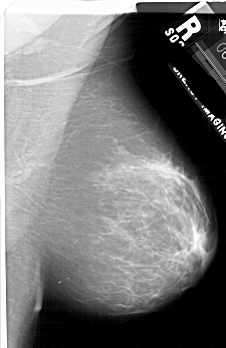

A_1758_1.LEFT_CC

LEFT_CC LINES 5296 PIXELS_PER_LINE 3496 BITS_PER_PIXEL 12 RESOLUTION 43.5 OVERLAY